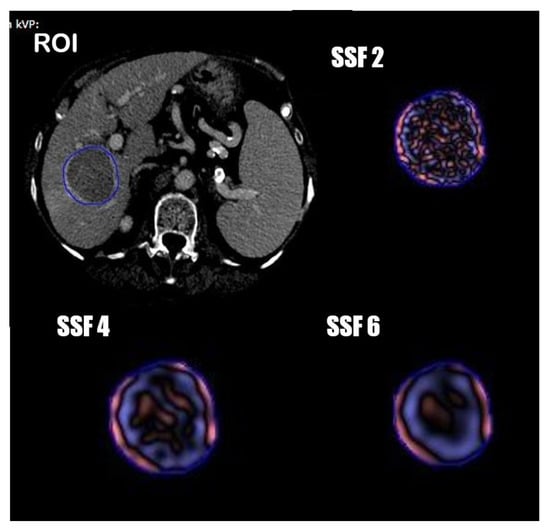

2.3. Texture Analysis

One radiologist and one resident in consensus manually segmented the tumor volumetric region of interest (VOI) on axial portal phases of the pre-treatment CT images, always considering the arterial phase to compare the geometrical shape of the lesion. (Figure 1) Radiomics features were extracted from the obtained VOIs and analyzed with TexRAD, a proprietary software algorithm (TexRAD Ltd, Somerset, England, United Kingdom).The spatial scale filter (SSF) value was altered between 0 and 6, extrapolating CT intensity features of three different sizes: fine (between 0 and 2 mm), medium (between 3 and 4 mm) and coarse (between 5 and 6 mm). Then, the following histogram parameters were extracted with every filter: mean, standard deviation, mean value of positive pixels (MPP), skewness, entropy, and kurtosis. In the final analysis, 18 features were extracted and analyzed.

Figure 1. Segmentation process and spatial scale filters (SSF) application.